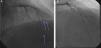

Aspirin 325 mg and clopidogrel 600 mg were given in the emergency room (ER), and intravenous heparin and nitroglycerin drips were started. From the ER, the patient was taken to the cardiac catheterization laboratory. Cardiac catheterization was performed within one hour of symptom onset through the right common femoral artery. Left coronary angiography revealed complete occlusion of the distal left anterior descending artery (LAD), second diagonal artery (D2) and second obtuse marginal (OM2) artery (Figures 2A and 3A). These lesions were crossed with coronary guide wires and treated by intracoronary aspiration with an Export aspiration catheter. Multiple large emboli were removed from the distal LAD, D2 and OM2. After aspiration, all vessels were fully reperfused (Figures 2A and 3A).

Figure 2.

(A) Emergency coronary angiogram on hospital admission showing total occlusion of the left anterior descending, second diagonal artery and second obtuse marginal arteries (arrows); (B) after successful intracoronary aspiration by aspiration catheter, the lesions were fully reperfused.

(A) Complete occlusion of the large second obtuse marginal branch; (B) successful intracoronary aspiration by suction catheter; the lesion was fully reperfused.